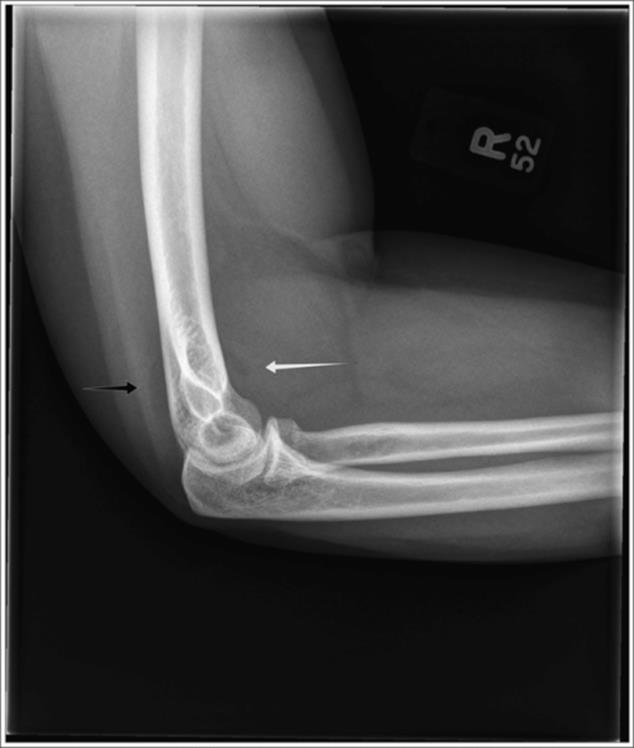

o Type I: fractures without displacement (62%) (Figure 2.11)

Figure 2.11 Mason Type I fracture of the radial head. Note the presence of a posterior fat pad and a displaced anterior fat pad suggestive of an effusion and occult fracture. Upon close inspection, a radial head fracture is noted. (Reproduced with permission of the Department of Emergency Medicine, Feinberg School of Medicine, Northwestern University.)